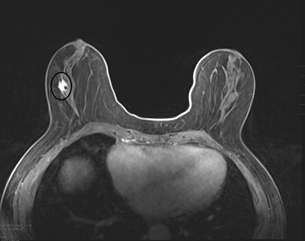

- MRI:

MRI is the most sensitive modality to detect ILC especially for detecting bilateral cancers, with a sensitivity of 93-95%. The most common presentation is a solitary mass with spiculated or irregular margins (95%). Non-mass enhancement is less common (69%)1. On Kinetic imaging, there will be delayed enhancement and less washout in the delayed phase when compared to that of IDC. If a patient has biopsy proven ILC, often the next step is to get an MRI to examine the contralateral breast as ILC is often multifocal and multicentric.

Case 1: